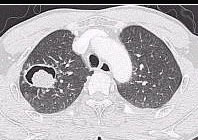

- 单项选择题女性,32岁。1个月前诊断为系统性红斑狼疮, 经激素治疗症状稍好转。近3天发热、咳嗽、咳少许粘痰。体检:肺呼吸音粗, 无啰音。胸部CT示右下肺邻近胸膜处结节影。结节影呈晕轮征(ha1osign)(如图),最可能的诊断是 ( )